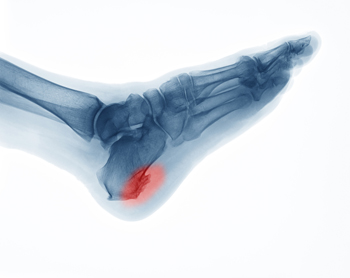

Sever’s disease is also known as calcaneal apophysitis, which is a medical condition that causes heel pain I none or both feet. The disease is known to affect children between the ages of 8 and 14.

Sever’s disease occurs when part of the child’s heel known as the growth plate (calcaneal epiphysis) is attached to the Achilles tendon. This area can suffer injury when the muscles and tendons of the growing foot do not keep pace with bone growth. Therefore, the constant pain which one experiences at the back of the heel will make the child unable to put any weight on the heel. The child is then forced to walk on their toes.